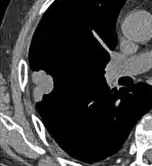

Lung nodule abutting a pulmonary cyst.[9]

• A lung nodule abutting a pulmonary cyst is a rare finding, yet indicating cancer.[9]